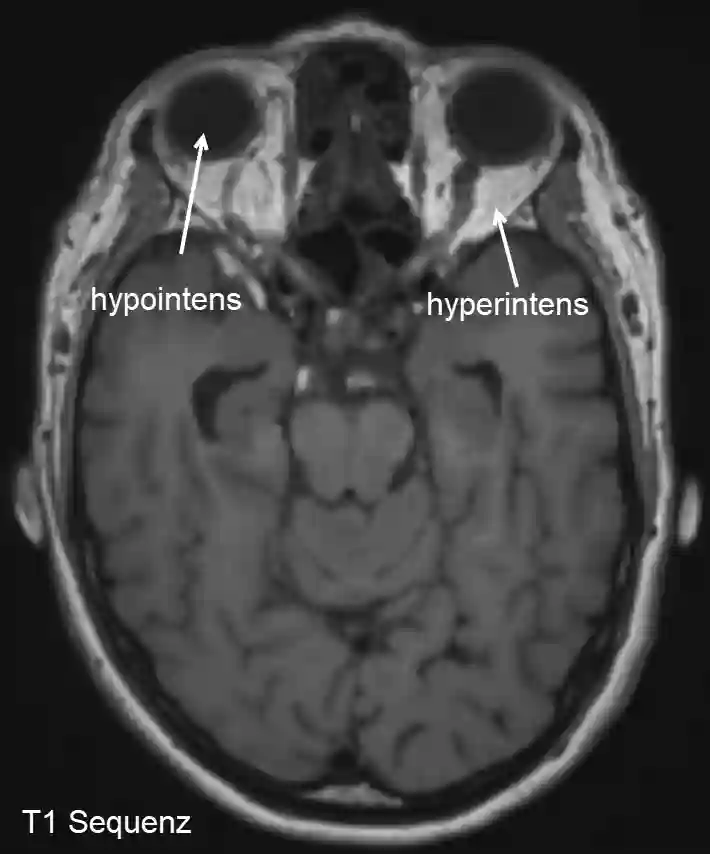

Hyperintense Bereiche sehen auf dem MR-Bild heller aus.

Hyperintensität und Hypointensität im MRI